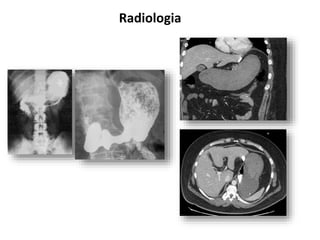

Radiologia